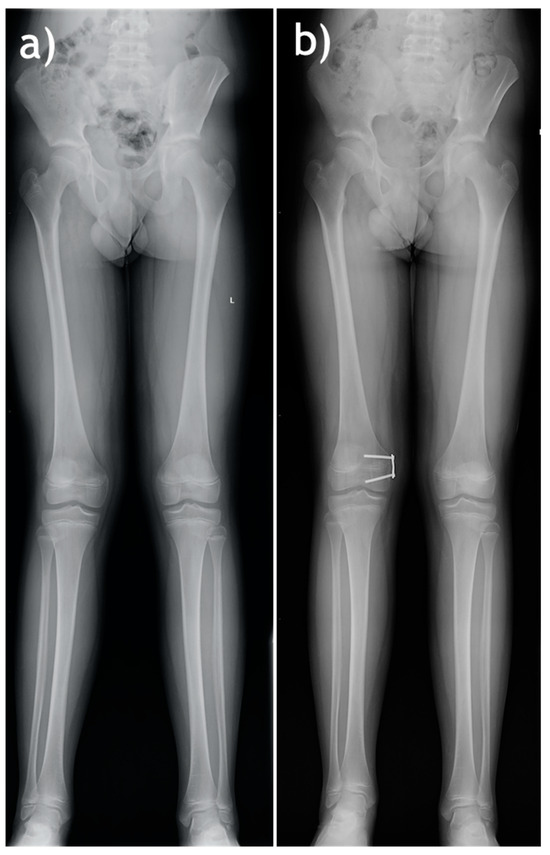

Each surgical procedure was conducted by one of two experienced orthopedic surgeons. All hemiepiphysiodesis procedures were conducted in children with open growth plates, with the use of O-Plate PediPlates implants (OrthoPediatrics, Warsaw, IN, USA) comprising two cannulated screws and a plate with two screw holes, Figure 1.

Figure 1. A sample patient with genu valgum—preoperative (a) and follow-up after hemiepiphysiodesis (prior to implant removal) X-ray images (b).